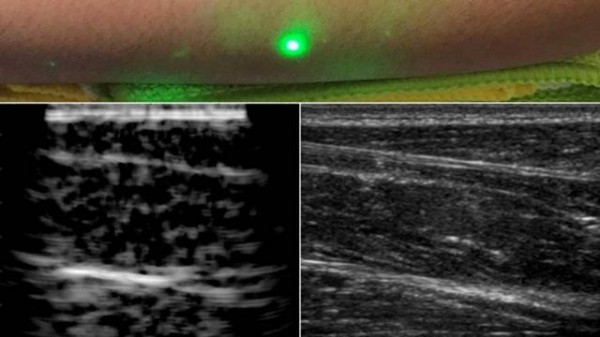

麻省理工學院設(shè)計了一種新方法,并使用激光超聲產(chǎn)生了第一批圖像。這項新技術(shù)不需要與身體接觸即可看到患者體內(nèi)。該技術(shù)使用對眼睛和皮膚安全的激光系統(tǒng)。系統(tǒng)中的一個激光可以遠程產(chǎn)生聲波,通過身體反彈。第二個激光遠程探測反射波,這些反射波被轉(zhuǎn)換成與傳統(tǒng)超聲波相似的圖像。

在測試中,研究人員用半米外聚焦在志愿者身上的遠程激光,掃描了幾位志愿者的前臂,并能夠觀察到皮膚以下6厘米深的組織特征,例如肌肉,脂肪和骨骼。這些圖像可與傳統(tǒng)超聲相媲美。

研究小組使用1550nm激光,這種波長被水高度吸收,對眼睛和皮膚都是安全的。激光產(chǎn)生清晰可見的脂肪,肌肉和組織邊界的圖像。該團隊計劃改進該技術(shù),并對其進行完善以解決功能上的缺陷。他們還希望提高激光的探測能力。在未來,他們希望改進現(xiàn)有設(shè)備,成為便攜式設(shè)備。